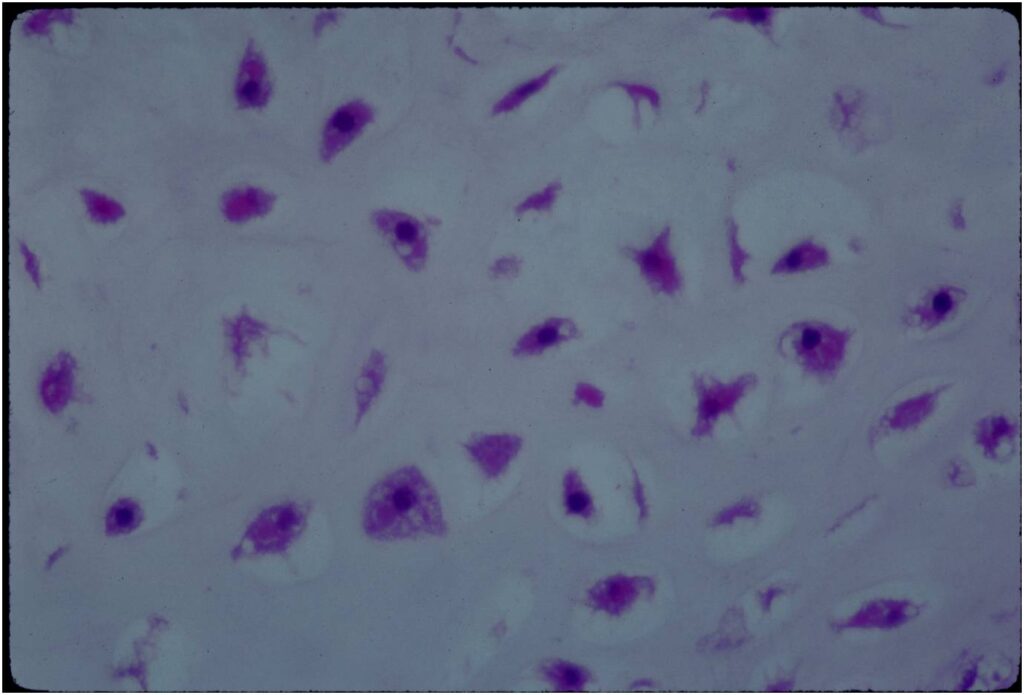

Microscopic Pathology

- Enchondromas are well defined lesions with cartilage arranged in lobules that are separated by fibrovascular septa

- Enchondral ossification may occur around periphery of lobules and when calcified appear as “Rings and Arcs” on X-rays

- Cells are in lacunae and have small dark nuclei

- Low cell count, cells appear bland with few chondrocytes and are similar size and shape

- Although some enchondromas may have areas that are hypercellular and may have two or three cells within a lacunae

- No entrapment or destruction of trabeculae

- There should be no myxoid change in long bone lesions (there is occasional myxoid change in enchondromas of the digits)

- Presence of myxoid change is sign of malignancy

- Enchondromas of digits can have hypercellularity, bi and trinucleated cells and myxoid change and still be considered benign

Microscopic Pathology

- Hypercellular with large number of binucleated chondrocytes

- Higher degree of cellularity and atypia compared to isolated enchondroma